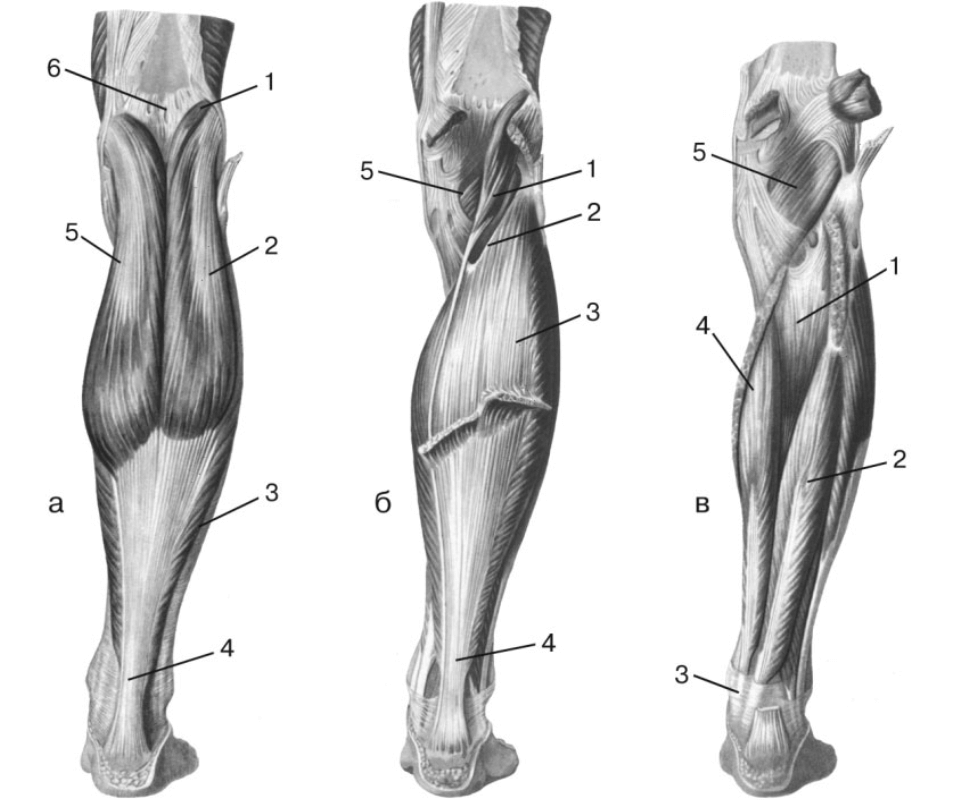

Анатомия подошвенной мышцы голени: подробное рассмотрение